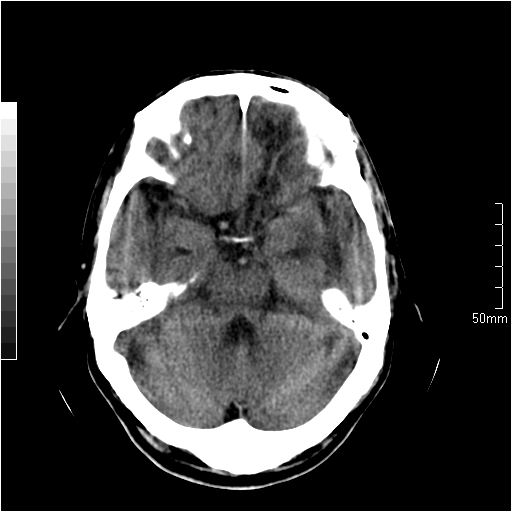

以下是引用天南地北在2007-6-25 12:39:00的发言:[br]有占位效应[br]支持术后复发

以下是引用zjzjr在2007-6-25 12:38:00的发言:[br]左侧复发,右侧转移。